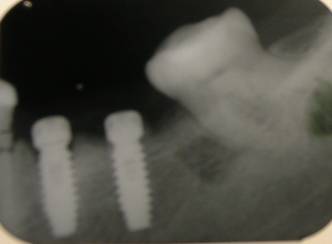

RADIOGRAFÍAS EN DISTINTAS ETAPAS DE IMPLANTACIÓN

Pre-Implante Inmediato post-implantes

Implantes óseo integrados, a los 17 meses